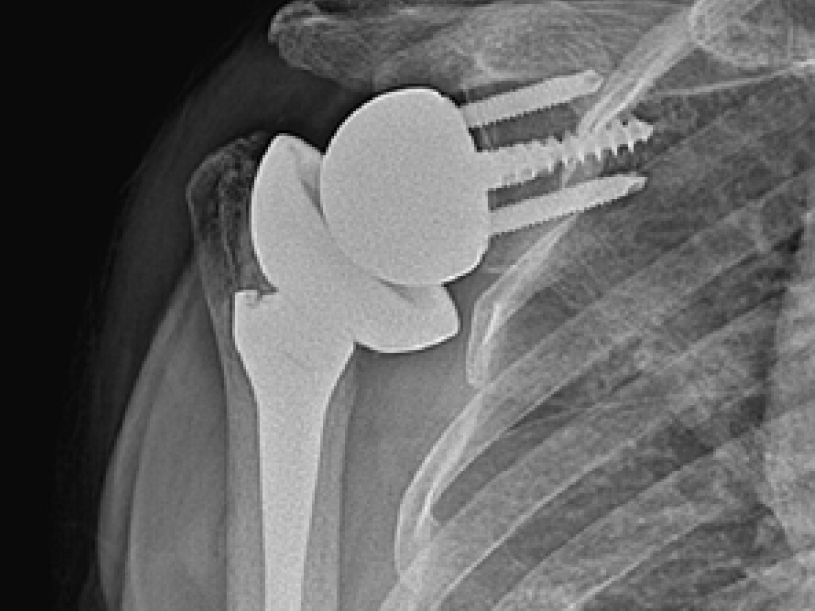

인공관절수술이란?

인공관절 수술은 연골 파열이나 퇴행성 변화로 인해 관절이 닳거나 손상된 경우,

손상된 부위를 제거한 후 인공관절로 대체하는 수술 방법입니다.

연골 손상이 지속되면 움직이지 않아도 통증이 발생할 수 있으며, 약물치료, 주사치료, 물리치료에도

증상이 호전되지 않는 관절염 말기 환자나 무혈성 괴사 환자에게 시행됩니다.

인공관절 수술

어깨 인공관절 수술 후

어깨 인공관절 수술 후 이미지

1. 통증을 줄이고 관절 운동을 원활하게 할 수 있도록 검증된 치료법

2. 최신 신소재를 활용한 인공관절은 마모가 적어 수명이 더욱 길어짐

3. 여성 맞춤형 인공관절이 개발되어 통증을 줄이고 회복 시간을 단축해 여성 환자의 만족도를 높임

4. 무릎뿐만 아니라 엉덩이관절(고관절), 어깨, 팔꿈치, 발목 등에도 인공관절 치환술을 시행